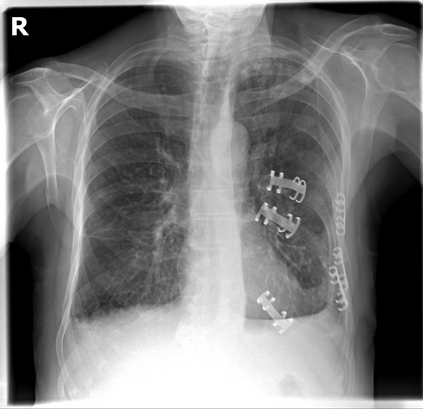

The evaluation of infectious disease processes on radiologic images is an important and challenging task in medical image analysis. Pulmonary infections can often be best imaged and evaluated through computed tomography (CT) scans, which are often not available in low-resource environments and difficult to obtain for critically ill patients. On the other hand, X-ray, a different type of imaging procedure, is inexpensive, often available at the bedside and more widely available, but offers a simpler, two dimensional image. We show that by relying on a model that learns to generate CT images from X-rays synthetically, we can improve the automatic disease classification accuracy and provide clinicians with a different look at the pulmonary disease process. Specifically, we investigate Tuberculosis (TB), a deadly bacterial infectious disease that predominantly affects the lungs, but also other organ systems. We show that relying on synthetically generated CT improves TB identification by 7.50% and distinguishes TB properties up to 12.16% better than the X-ray baseline.